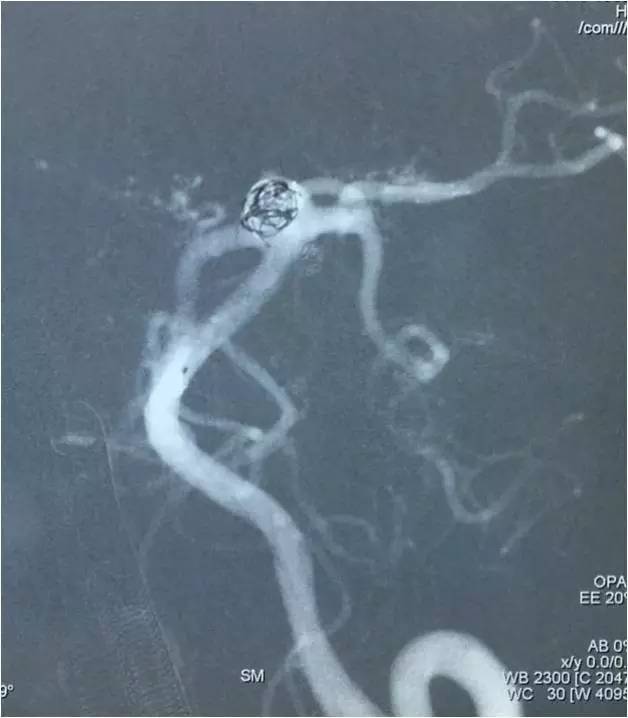

下面是术后各个角度的左椎动脉造影,可见基底动脉顶端动脉瘤和左小脑上动脉瘤完全栓塞,载瘤动脉畅通。基底动脉顶端动脉瘤的子瘤终于被消灭。

▼术后左椎动脉造影正位反汤28度。

▼纯正位。

▼侧位。

▼正位汤46度。